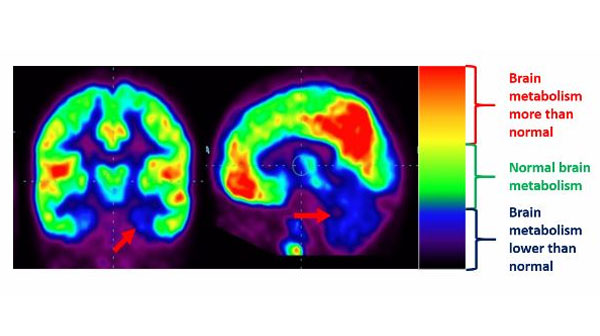

Positron Emission Tomography – Computed Tomography (PET-CT) scan is a technique of functional imaging of the brain. PET-CT scan is performed by injecting radioactive dye intravenous and then the amount of dye absorbed by the brain tissue is recorded. The radioactive dye is similar to glucose in its composition and hence is readily absorbed by the brain cells.

The results will be given to you in two forms, first a print of the films and a CD containing the entire PET-CT study and second an interpretation and report by a nuclear medicine expert after having analyzed the study. This study will show the areas of the brain that are functioning lower than normal (hypofunctioning) as well as more than normal function (hyperfunctioning).

Research has implied that there could be problems related to the functioning of the temporal lobes of the brain, including hippocampus and amygdala. These areas are responsible for organizing sensory input, auditory perception, language and speech production, memory association formation and emotional expression etc. These co-relate to the kind of issues seen in Autism. Another area, which appears to be affected, is the cerebellum, which is important for information processing, balance and coordination.